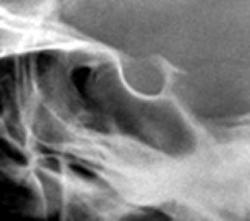

Иллюстрация 6. Изолировано выделена область турецкого седла, произведено увеличение изображения.